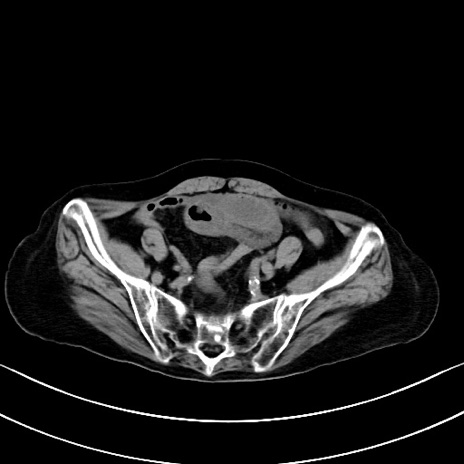

症例40(横断像)他院1日前

横断像